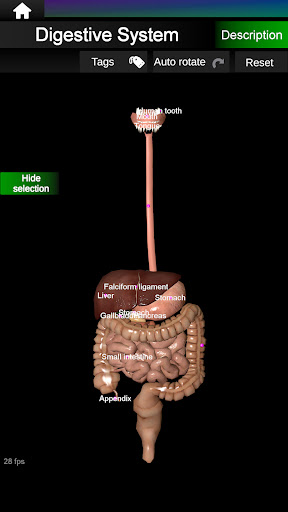

* Травна система, включаючи шлунок, тонку кишку, товсту кишку та анімацію цієї системи.

* Легкий доступ і навігація (масштабування, 3D-обертання).

* Приховати або показати інформацію.

* Описи кожного органу.

* Нова опція плаваючих етикеток.